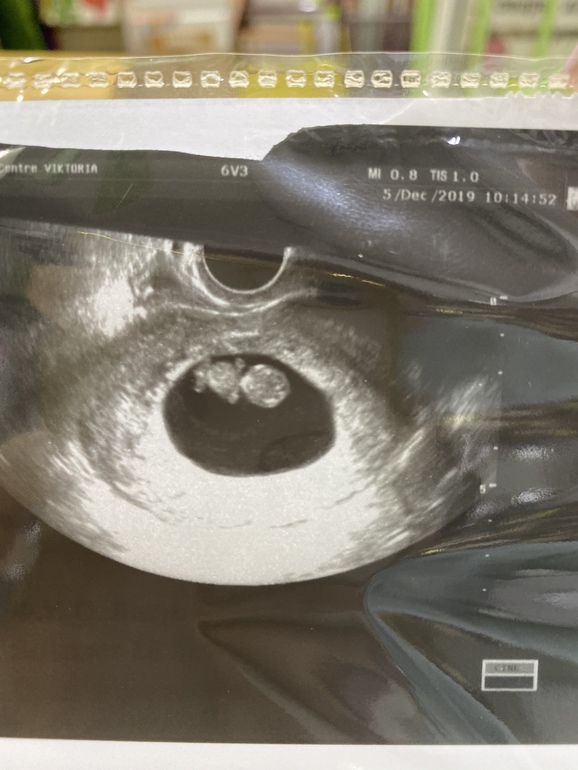

С утра сразу давай искать узи недалеко от дома - благо, нашла в соседнем квартале. Аппарат там конечно🤦🏻♀️ допотопный. Слава богу, с малышом всё хорошо😌 ктр 24мм, что соответствует 9н1д - пуля в пулю по О. Сердечко включили ❤️ на этот раз обошлось без слёз😂 179 уд/мин. Такой головастик🥰 чудо наше) доктор узи заметила даже шевелюшки, говорит «он в начале хвостиком вилял😅» поняла, что мне интересно тоже посмотреть, навела датчик и замерла😇 не заметили, естессно ничего) ну хоть попробовали😅

но мне фотку дали совсем не такую красивую - не детальную, как у вас)